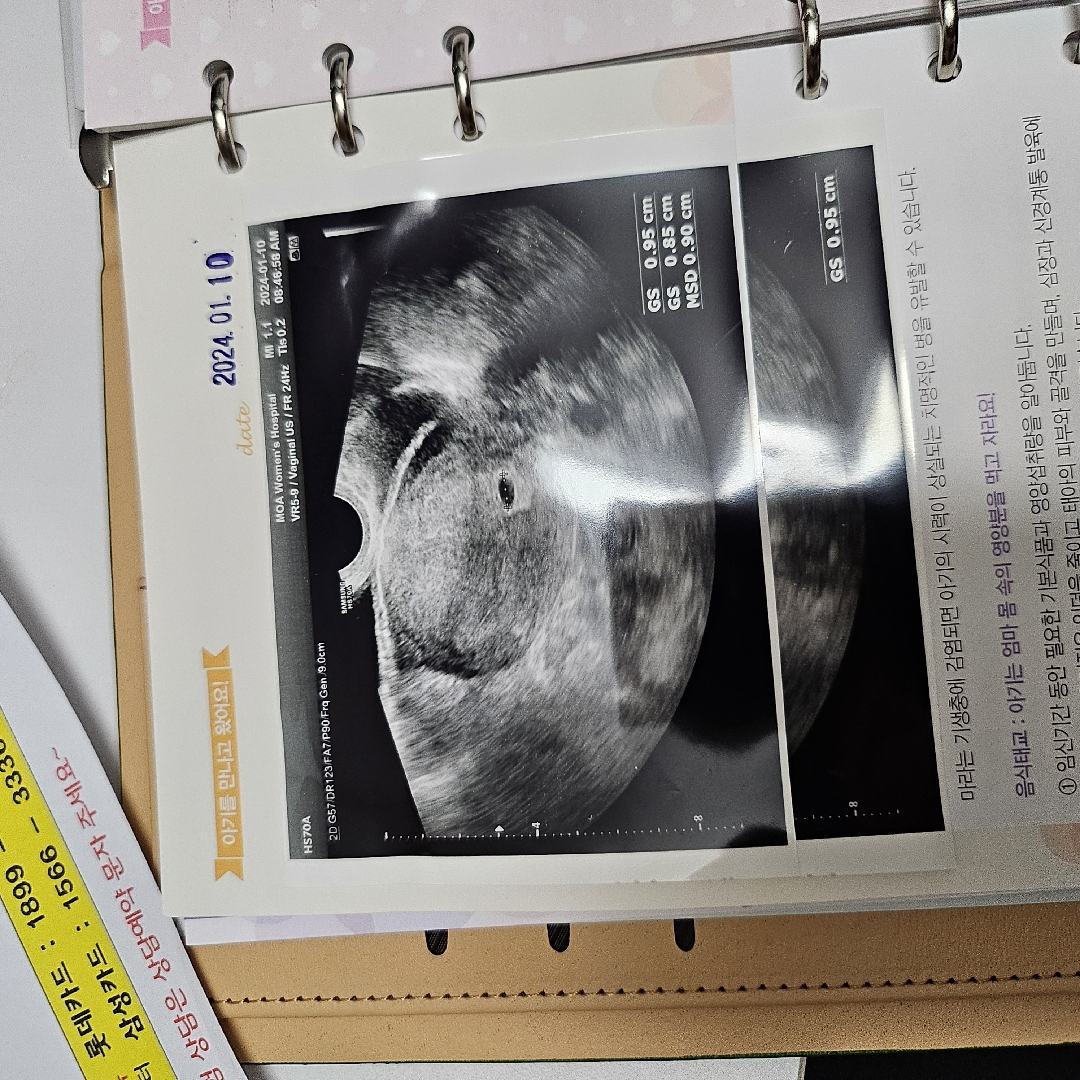

네이버기준 5주4일

막생 12/2 네이버기준으로 5주 4일차에요 병원에선 5주 3으로잡아쥬셧어요 아침에 아기집 보고 산모수첩 임산부 등록하고왔어용 국민행복카드 ㅎㅖ택은 어디가좋을가요? 만드려는데 고민되네요ㅠㅠ

아니요 그런말 안하시구 그냥아기집 이쁘게잡혔다고? 2주뒤심장이랑 들으러오라해써요ㅜㅜ